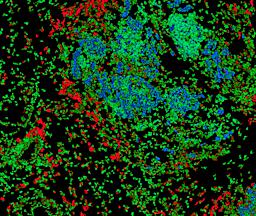

Pancreatic ductal adenocarcinoma is a lethal disease with limited treatment options and poor survival. We studied 83 spatial samples from 31 patients (11 treatment-naïve and 20 treated) using single-cell/nucleus RNA sequencing, bulk-proteogenomics, spatial transcriptomics and cellular imaging. Subpopulations of tumor cells exhibited signatures of proliferation, KRAS signaling, cell stress and epithelial-to-mesenchymal transition. Mapping mutations and copy number events distinguished tumor populations from normal and transitional cells, including acinar-to-ductal metaplasia and pancreatic intraepithelial neoplasia. Pathology-assisted deconvolution of spatial transcriptomic data identified tumor and transitional subpopulations with distinct histological features. We showed coordinated expression of TIGIT in exhausted and regulatory T cells and Nectin in tumor cells. Chemo-resistant samples contain a threefold enrichment of inflammatory cancer-associated fibroblasts that upregulate metallothioneins. Our study reveals a deeper understanding of the intricate substructure of pancreatic ductal adenocarcinoma tumors that could help improve therapy for patients with this disease.